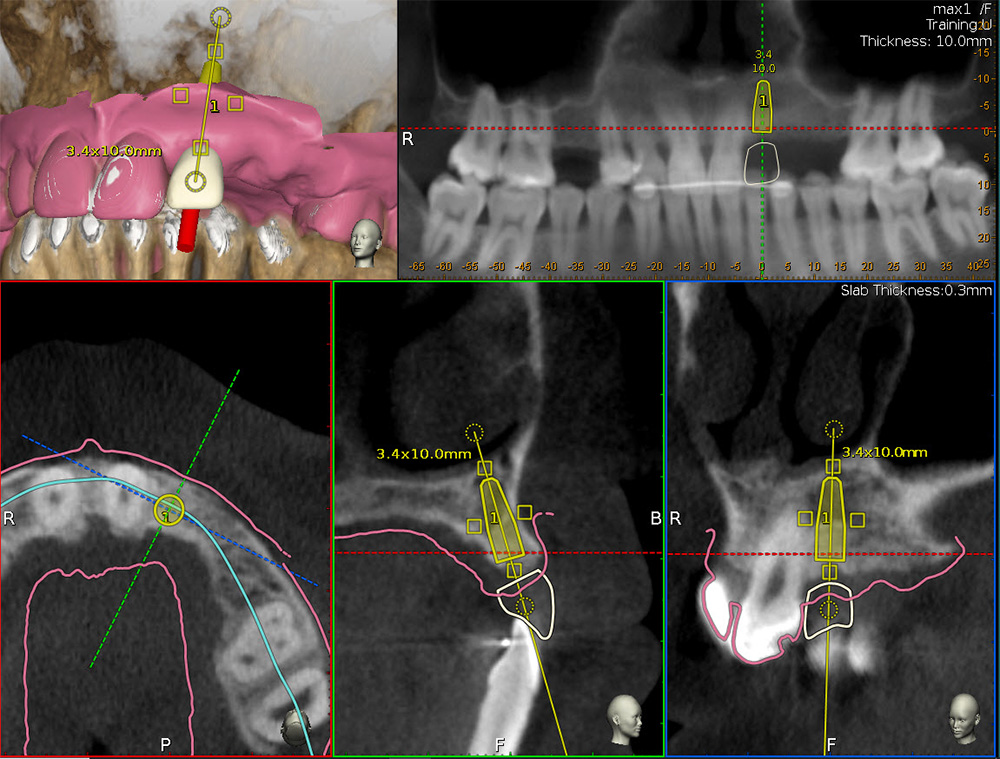

Calibration In Dynamic Navigation Surgery In Implamt

Browse our specialized Calibration In Dynamic Navigation Surgery In Implamt portfolio with numerous expertly curated photographs. optimized for both digital and print applications across multiple platforms. providing reliable visual resources for business and academic use. Each Calibration In Dynamic Navigation Surgery In Implamt image is carefully selected for superior visual impact and professional quality. Perfect for marketing materials, corporate presentations, advertising campaigns, and professional publications All Calibration In Dynamic Navigation Surgery In Implamt images are available in high resolution with professional-grade quality, optimized for both digital and print applications, and include comprehensive metadata for easy organization and usage. Our Calibration In Dynamic Navigation Surgery In Implamt collection provides reliable visual resources for business presentations and marketing materials. Whether for commercial projects or personal use, our Calibration In Dynamic Navigation Surgery In Implamt collection delivers consistent excellence. The Calibration In Dynamic Navigation Surgery In Implamt archive serves professionals, educators, and creatives across diverse industries. Regular updates keep the Calibration In Dynamic Navigation Surgery In Implamt collection current with contemporary trends and styles. Advanced search capabilities make finding the perfect Calibration In Dynamic Navigation Surgery In Implamt image effortless and efficient. Multiple resolution options ensure optimal performance across different platforms and applications.